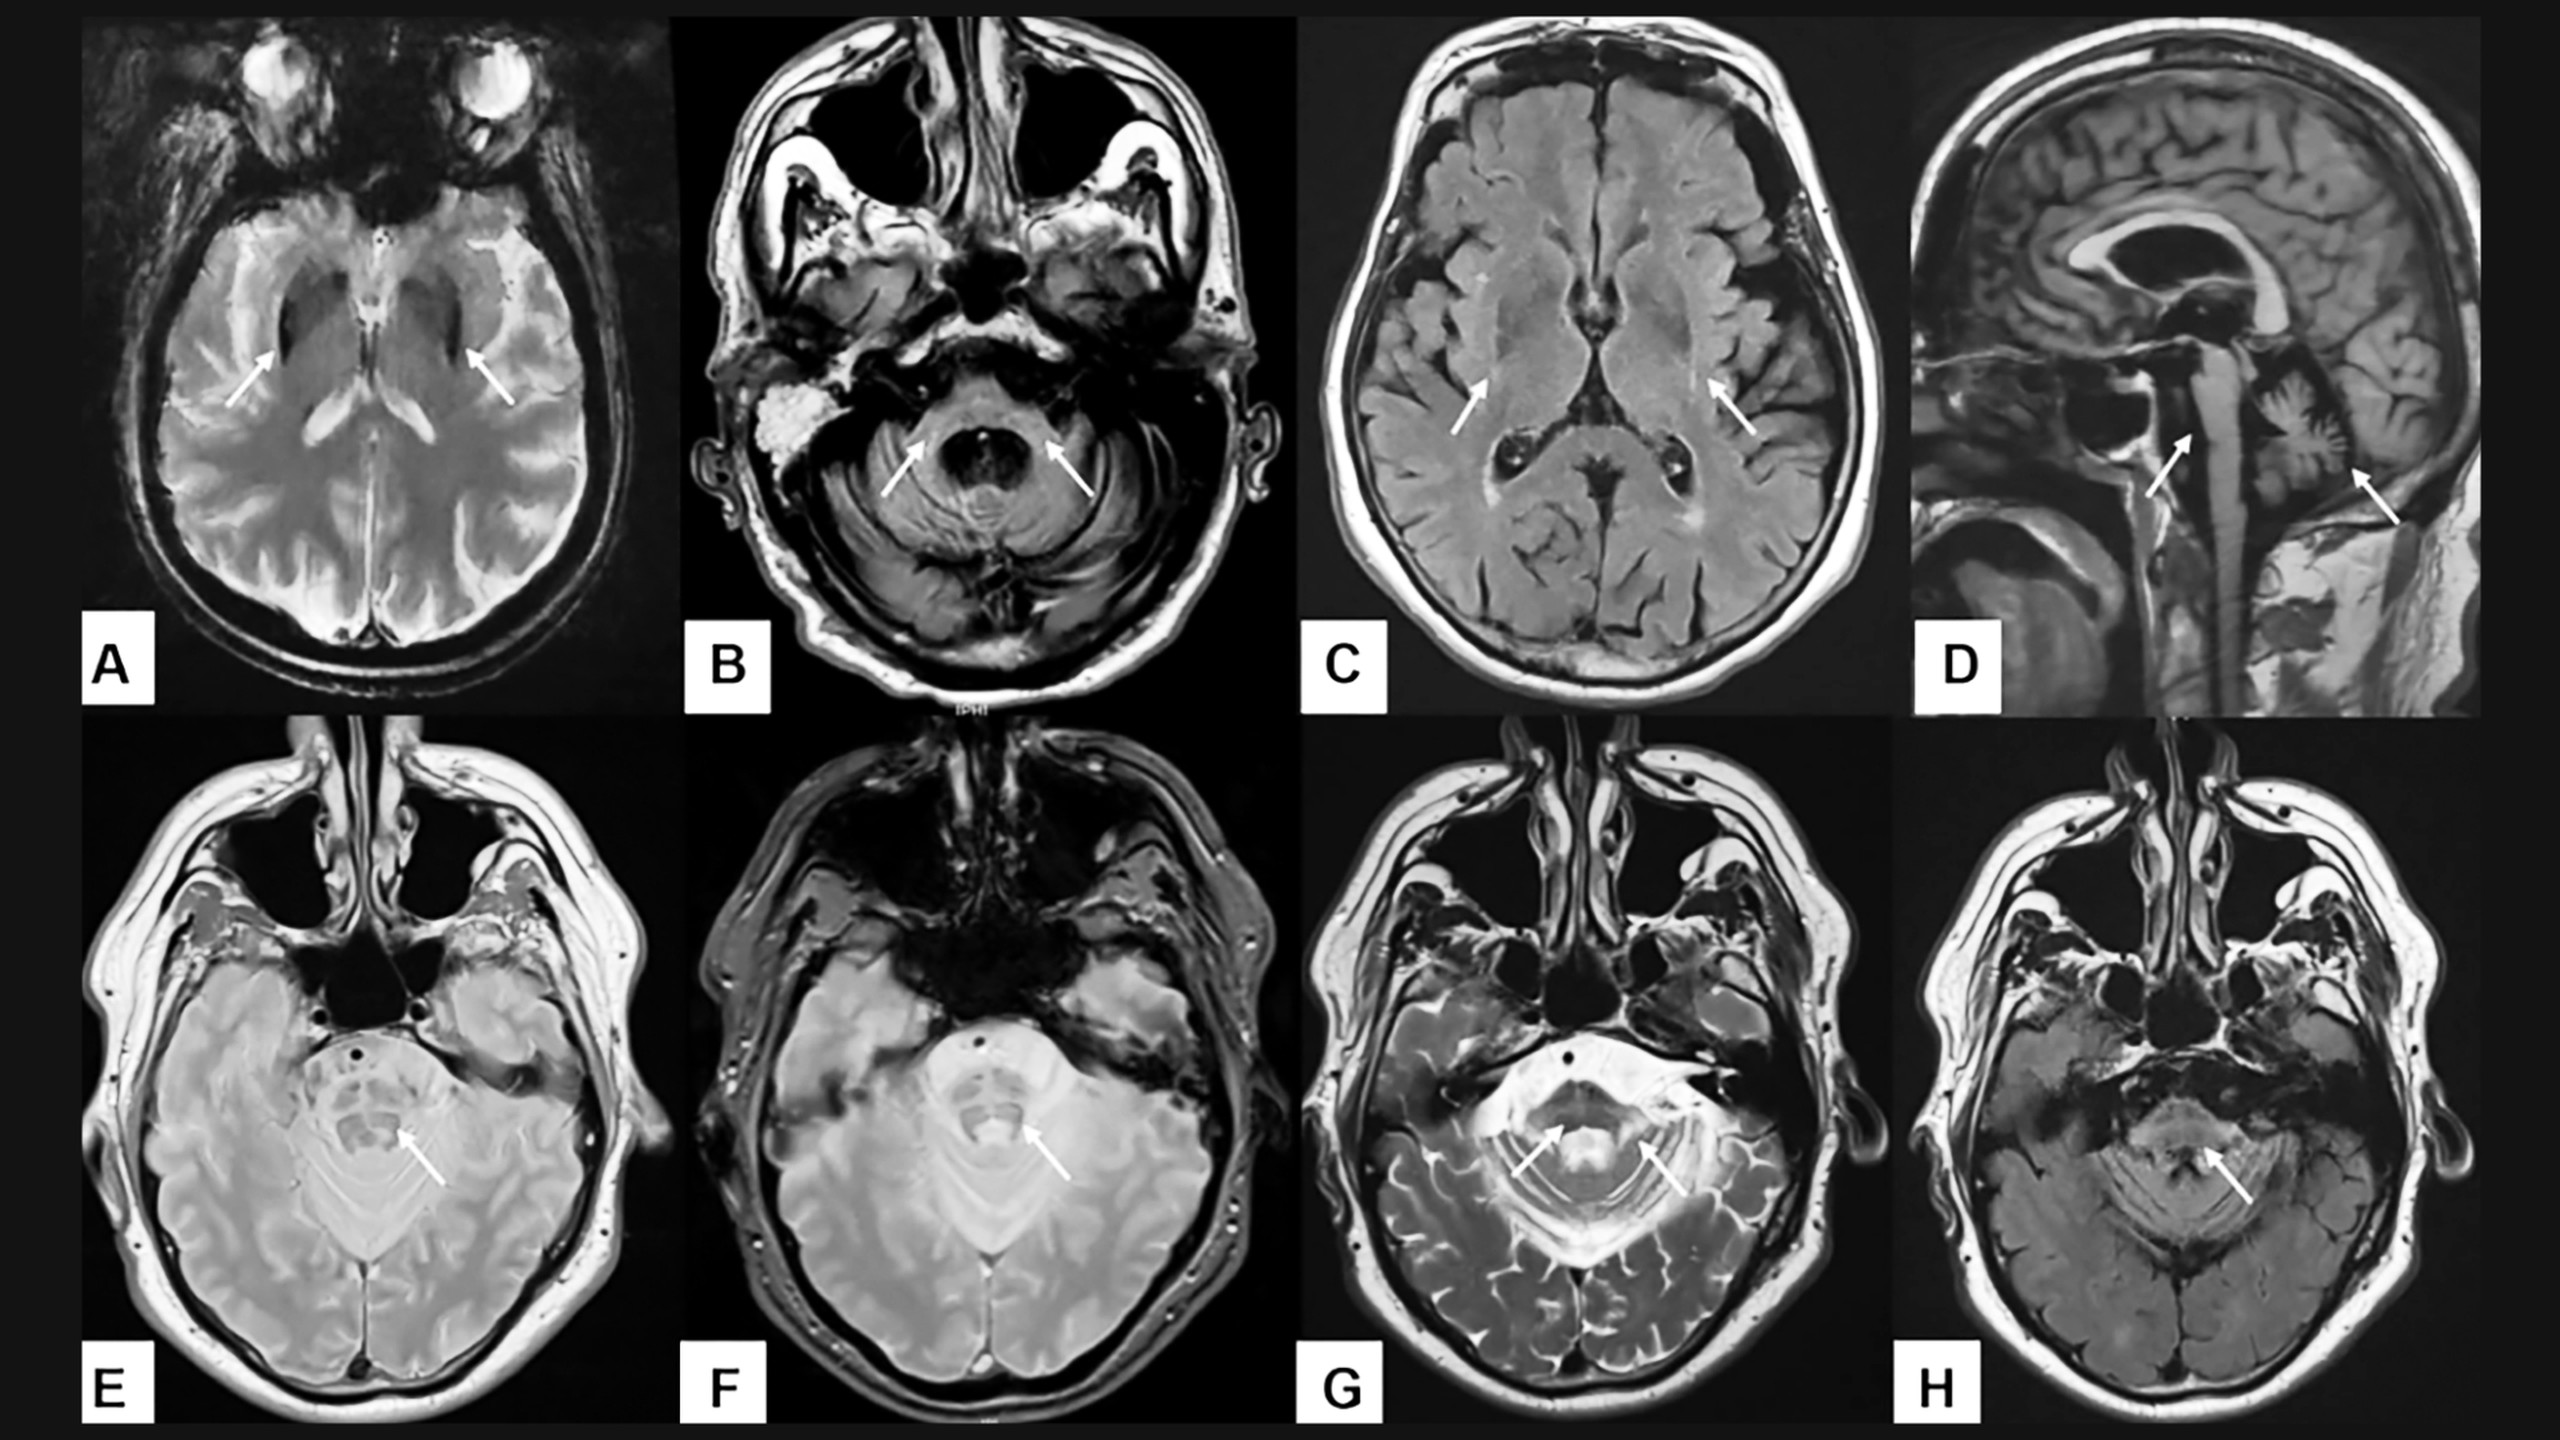

Chẩn đoán bệnh teo đa hệ thống thường dựa trên sự kết hợp giữa suy giảm thần kinh tự chủ và các triệu chứng liên quan đến tiểu não hoặc hội chứng parkinson. Khi nghi ngờ teo đa hệ thống, bác sĩ sẽ kiểm tra các phản xạ và chức năng cơ thể như bàng quang và huyết áp. Hiện tại, không có xét nghiệm cụ thể để chẩn đoán bệnh nhưng chụp MRI não thường được chỉ định để phát hiện tổn thương não và phân biệt MSA thể tiểu não và thể parkinson.